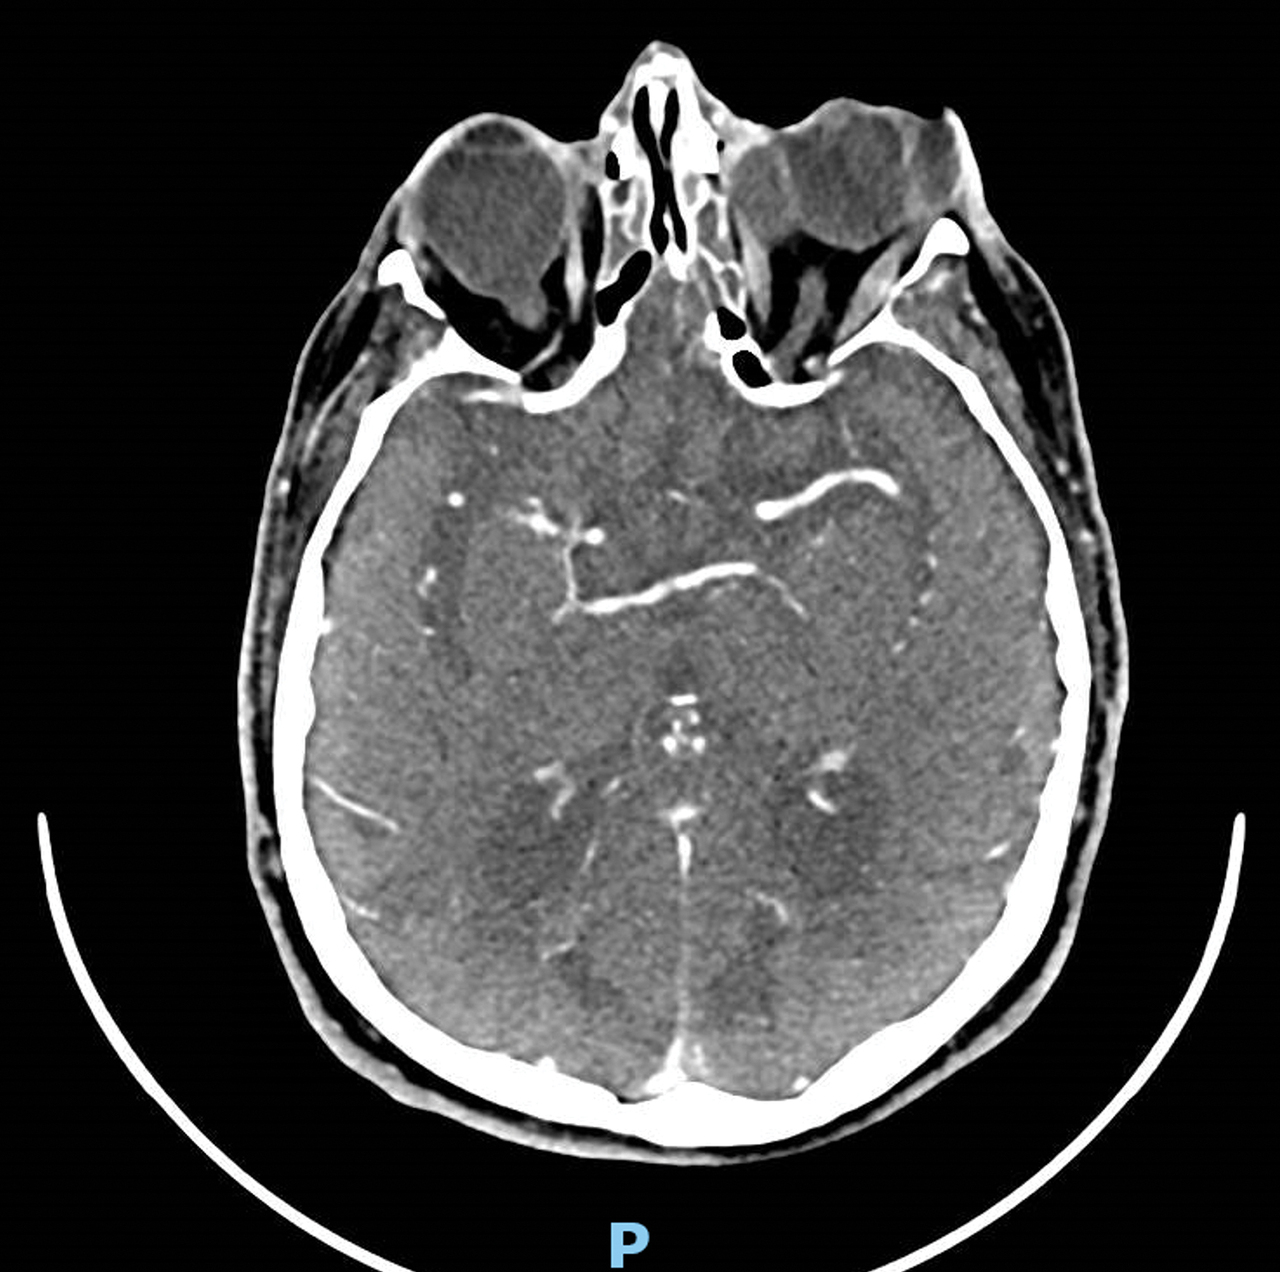

Un homme de 77 ans se plaint de céphalées et d’une douleur orbitaire gauche dans les suites d’une intervention pour décollement de rétine. La protéine C réactive (CRP) est à 100 mg/L. Il reçoit un traitement antibiotique en collyre sans efficacité. Un scanner est réalisé.

Le scanner montre un abcès orbitaire gauche localisé associé à un comblement des cellules ethmoïdales antérieures.